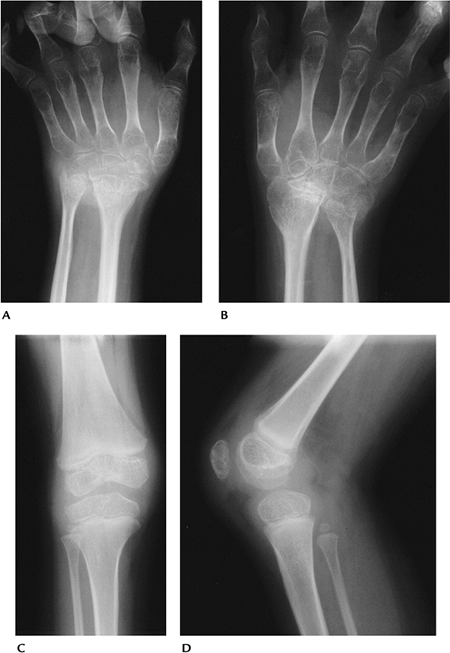

FIGURE 13-22 Juvenile chronic arthropathy. (A,B) AP radiographs of the wrists showing marked osteopenia with carpal collapse. AP (C) and lateral (D) radiographs of the knee showing epiphyseal hyperemia and soft tissue involvement (synovitis).

|